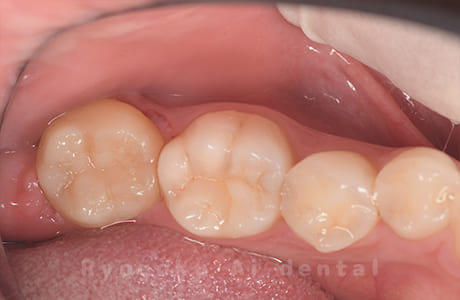

Case04

- 慢性根尖性歯周炎

- 治療内容

-

- 220,000円

他院で抜歯し、インプラントを進められた患者さんです。親知らずが残っていたため、移植治療がベストと判断し、治療を行いました。

<リスク・副作用>